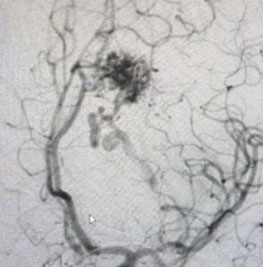

Angiogram (Figure 3 and 4) confirmed the presence of a deep left frontal AVM without any associated aneurysms.

Fig. 3